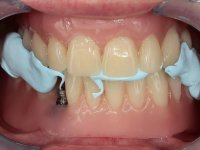

Two dental implants were planned in the CBCT scan, in the area of the inferior canines. The dental extractions were performed and, simultaneously, the alveolar crest was flattened and the implants were placed. Three issues were considered while implant placement: parallelism of the axis, same height of the implant’s neck, and same position in the coronal plan. This 3D insertion is essential to have a good retention of the overdenture in the future. Patient’s removable denture was fixed in the dental lab, to include the extracted teeth, and a soft-tissue relining was done over the healing abutments. After the osseo-integration period, a first impression was done with an open-tray and a doble-mix technique. This dental impression allowed the production of screwed wax-rims and an individual tray for a functional impression. A second impression, final, was done with an individual tray with a monophasic silicone. The occlusal wax-rims were correct in the mouth according to the full denture guidelines. Special care was taken with the occlusal vertical dimension and the support in the soft-tissues. A silicone bite registration material was used to better defined the intermaxillary relations. Teeth set-up was done in the dental lab with the selected tooth color. Due to the fact that the base was screwed to the dental implants, the teeth set-up was functionally evaluated in the mouth. Another silicone bite registration material was used to allow final occlusal adjustments. Finally, the locators were screwed and the retention nylons were selected according to the patient needs.